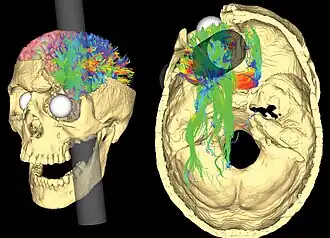

Psychologists generally consider biology the substrate of thought and feeling, and therefore an important area of study. Behaviorial neuroscience, also known as biological psychology, involves the application of biological principles to the study of physiological and genetic mechanisms underlying behavior in humans and other animals. The allied field of comparative psychology is the scientific study of the behavior and mental processes of non-human animals.[92] A leading question in behavioral neuroscience has been whether and how mental functions are localized in the brain. From Phineas Gage to H.M. and Clive Wearing, individual people with mental deficits traceable to physical brain damage have inspired new discoveries in this area.[93] Modern behavioral neuroscience could be said to originate in the 1870s, when in France Paul Broca traced production of speech to the left frontal gyrus, thereby also demonstrating hemispheric lateralization of brain function. Soon after, Carl Wernicke identified a related area necessary for the understanding of speech.[94]: 20–2

The contemporary field of behavioral neuroscience focuses on the physical basis of behavior. Behaviorial neuroscientists use animal models, often relying on rats, to study the neural, genetic, and cellular mechanisms that underlie behaviors involved in learning, memory, and fear responses.[95] Cognitive neuroscientists, by using neural imaging tools, investigate the neural correlates of psychological processes in humans. Neuropsychologists conduct psychological assessments to determine how an individual's behavior and cognition are related to the brain. The biopsychosocial model is a cross-disciplinary, holistic model that concerns the ways in which interrelationships of biological, psychological, and socio-environmental factors affect health and behavior.[96]